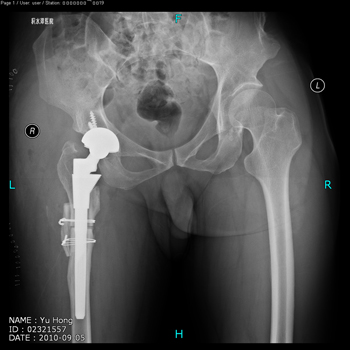

total hip replacement on hips with unilateral severe dysplasia and high riding